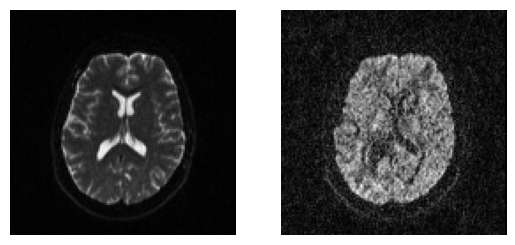

We can quickly visualize the results using matplotlib. For example, let’s show here the middle axial slices of volume 0 and volume 10.

Showing the middle axial slice without (left) and with (right) diffusion weighting.